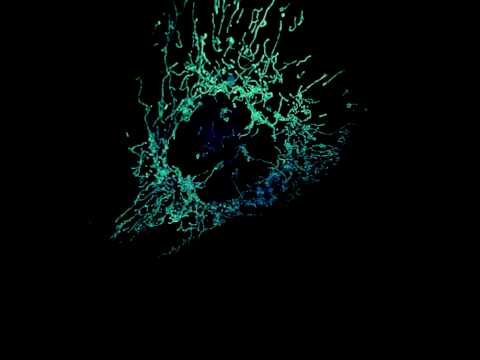

Mitochondrial network within a human osteosarcoma epithelial cell as seen by a new microscope being [...]